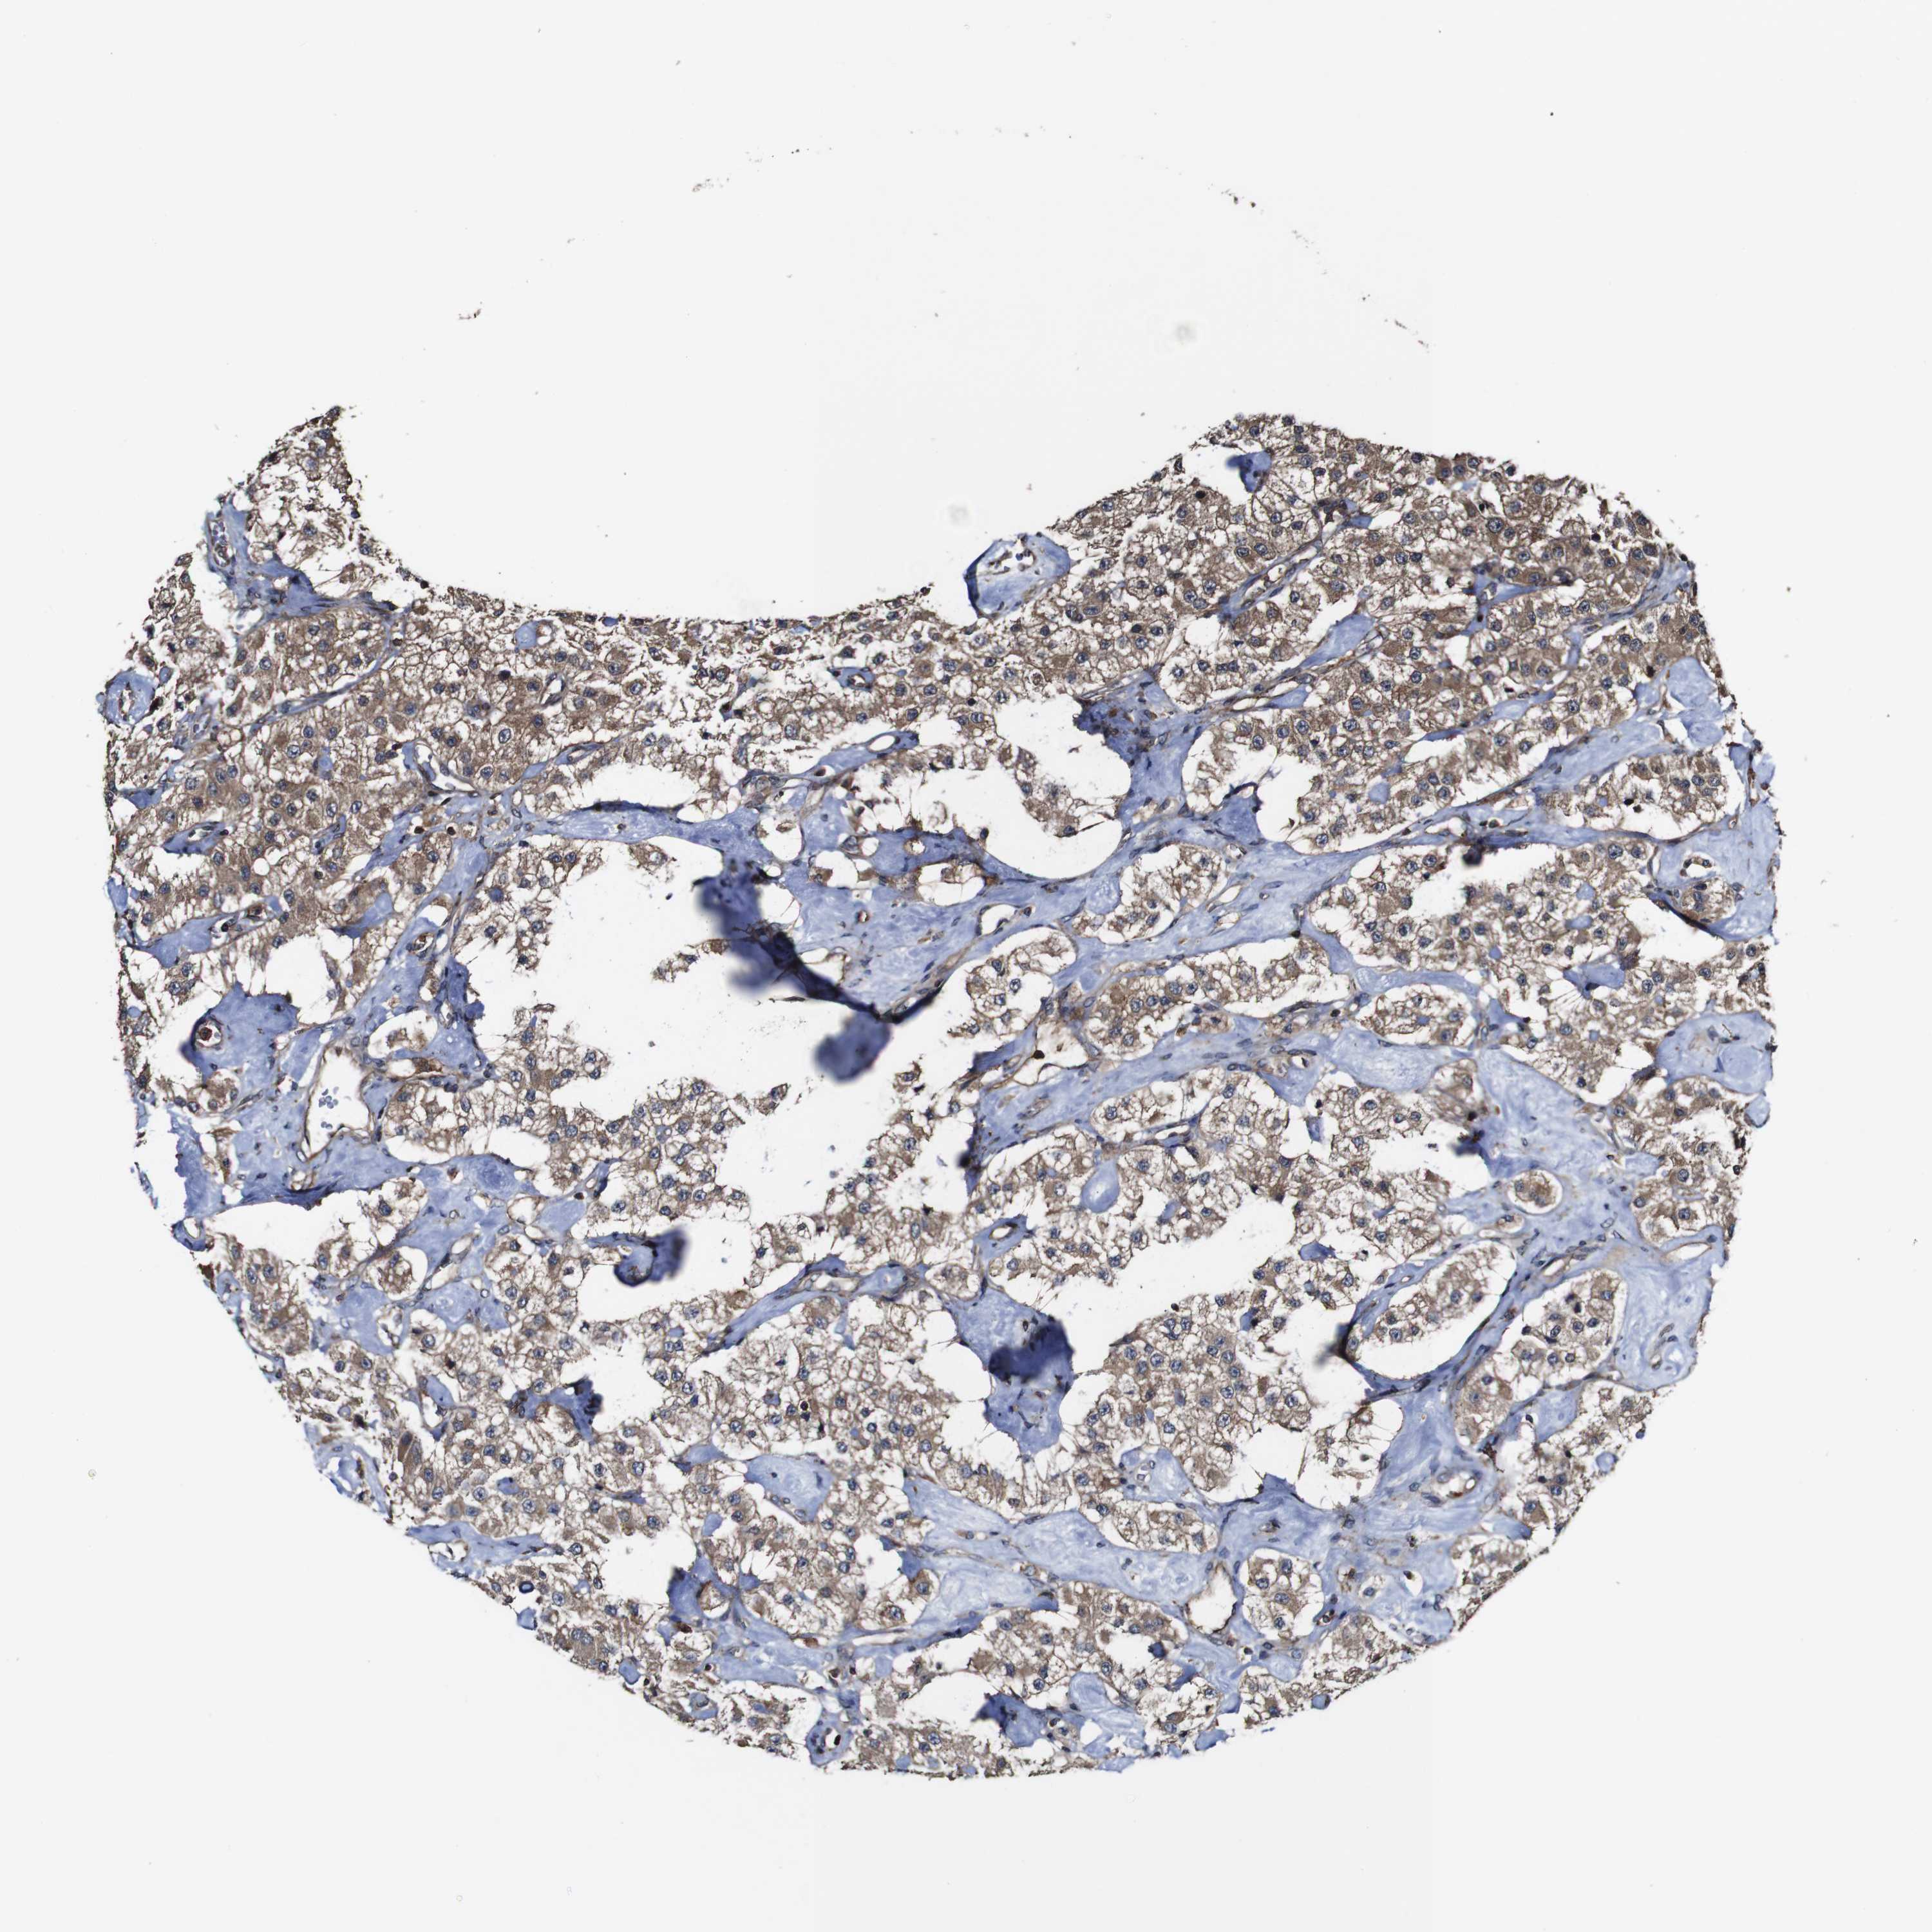

CARCINOID - Protein expressioni

A mouse-over function shows sample information and annotation data. Click on an image to view it in a full screen mode. Samples can be filtered based on level of antibody staining by selecting one or several of the following categories: high, medium, low and not detected. The assay and annotation is described here.

Each image is clickable and will lead to virtual microscopy that enables deeper exploration of all samples and also displays staining intensity scores, fraction scores and subcellular localization as well as patient and tissue information for each sample.

Antibody HPA012297

Staining

High

Intensity

Strong

Quantity

>75%

Location

Cytoplasmic/membranous

Carcinoid, malignant, NOS